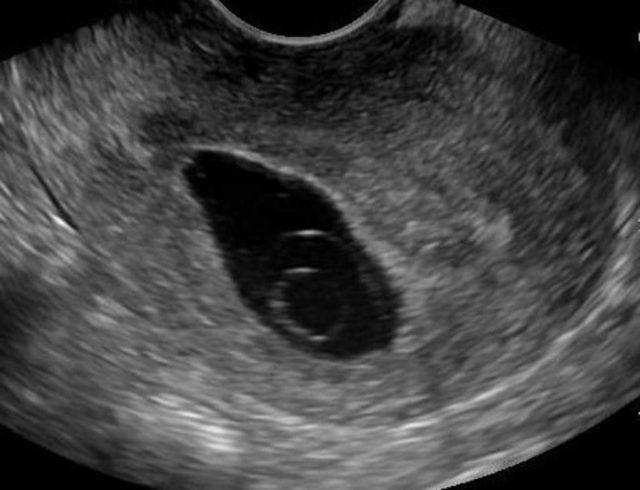

Karena itulah, Anda tetap membutuhkan pemeriksaan ultrasound (USG) untuk mendeteksi anembryonic pregnancy.

Untuk mendapatkan hasil yang lebih jelas, dokter mungkin mengusulkan pemeriksaan transvaginal ultrasound (USG melalui vagina).

Pemeriksaan untuk memastikan blighted ovum dengan USG umumnya dilakukan pada minggu ke 7–9 kehamilan karena saat inilah embrio seharusnya mulai terbentuk.